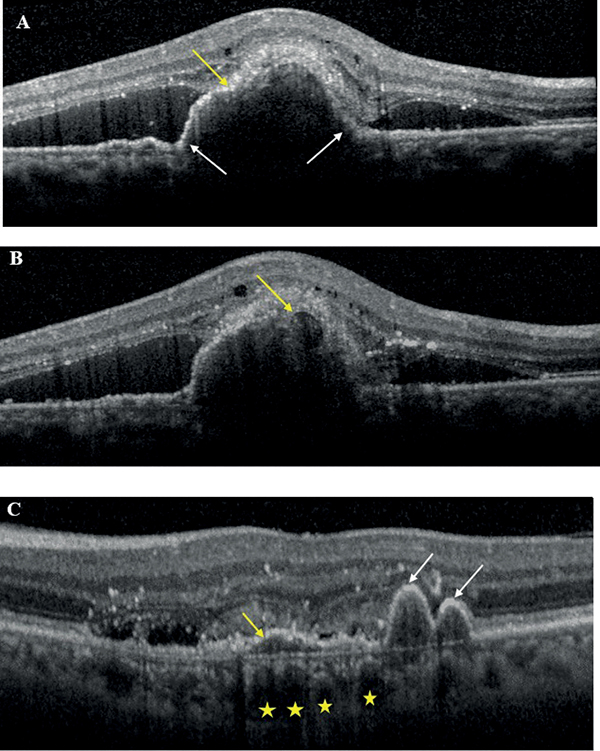

PCV esetén több meghatározó vizsgálat is született, amelyeket Permadi és munkatársai 2022-es metaanalízisben elemeztek, és azt találták, hogy pusztán OCT-vel az összevont szenzitivitás elérte a 91%-ot, míg a specificitás a 88%-ot PCV azonosítására. A legrelevánsabb OCT-eltéréseknek PCV esetén a következőket találták:

- hirtelen csúcsosodó PED (legalább egyik oldalán >70°, ismerhetjük még „hüvelykujj alakú” PED-ként is);

- hasadt PED;

- sub-pigmentepithelialis gyűrűszerű elváltozás;

- többszörös PED;

- DLS,

amelyek közül az első 3 a PCV OCT-n látható leggyakoribb, utóbbi kettő pedig kiegészítő jellemzője (9. ábra).

• A kép: hirtelen csúcsosodó PED (fehér nyilak), hasadt PED (sárga nyíl)

• B kép: subpigmentepithelialis gyűrűszerű elváltozás (sárga nyíl)

• C kép: többszörös PED (fehér nyilak), DLS (sárga nyíl), dilatált Haller-réteg-erek (sárga csillagok)